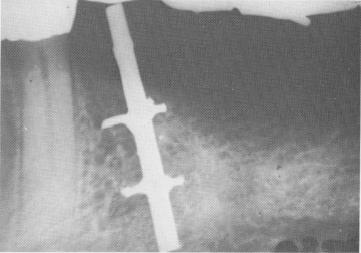

Fig. 5-21. An early Tramonte implant, a modified orthopedic screw with a broad two-piece head. Because of the large impact area, bone could not grow around the upper-most spires. (Courtesy S. Tramonte.)

The implants of the Italian Stefano Tramonte closely resemble the screws used by orthopedic surgeons. The wide head of Tramonte's first implants often produced poor results (Fig. 5-21). This wide head provided too broad an impact area and invited soft tissue invagination. In a later Tramonte design, the prosthesis-bearing shaft is narrower than the spiral portion (Fig. 5-22). With this type of design, as long as the operator inserts a good portion of the narrower shaft deep in bone, there is an excellent chance that bone will condense around the spirals and that the implant will be held quite secure (Figs. 5-23 and 5-24).